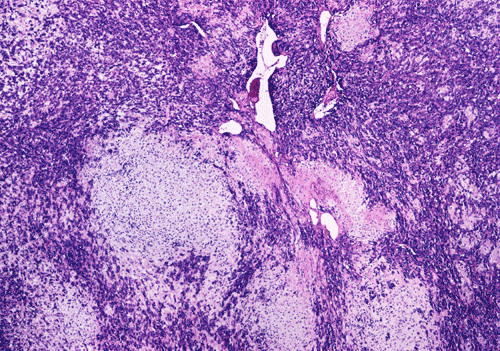

At low power magnification (Panel A and B), the tumor seems to have two distinct components. The first is a highly cellular, basophilic, background stroma. The second is islands of well-demarcated, pale bluish chondroid, hypocellular areas reminiscent of hyaline cartilage. Together, these two components impart a so-called "white clouds in blue sky" histologic appearance. At medium- and high power magnification (Panel C and D), the lacuna in the chondroid areas are well appreciated which helps to confirm the cartilaginous nature of these pale islands. Please note the impressive nuclear pleomorphism in the neoplastic chondrocytes (Panel D).

The basophilic background is composed of tightly packed, undifferentiated spindle cells without significant deposition of collagen fibers in between (Panel E). Panels  F, G, and H are taken from a different area of the tumor and were not posted on the question web-page. The pathologic change in these areas are very common among mesenchymal chondrosarcoma and should be looked. These include lobules of highly cellular tumor separated by fibrous connective tissue septa (Panel F) and Prominent tumor vascularity with highly branching vessels which (with a bit of imagination!) resemble deer "antlers" or "staghorns"(Panel G and H). This pattern of vessel distribution is similar to that seen in hemangiopericytoma (an uncommon soft tissue tumor) and is therefore often described as a “hemangiopericytoma-like” vascular pattern. The overall gross and light microscopic features in this case are consistent with a diagnosis of primary extraskeletal mesenchymal chondrosarcoma.

Histologically, the tumor is characterized by a bimorphic growth pattern in which islands of usually well-differentiated hyaline cartilage embedded in a background of basophilic primitive mesenchymal cells. This created the well-known “white clouds in blue sky” pictures of these tumors. In addition, hemangiopericytoma-like components are typically present [Dabska M & Huvos AG, 1983]. Mesenchymal chondrosarcoma differs from conventional chondrosarcomas in three different aspects. First, it tends to occur in young patients. Second, it has a predilection for the for the head and neck areas. Third, about one third of these cases occur in soft tissue. The articles by Arora & Riddle (2018) and Shakked RJ et al. (2012) are recommended.

Grossly, mesenchymal chondrosarcoma typically appears as a circumscribed, lobulated, solid mass with a soft, fleshy, grey-white to gray-pink cut surface. Scattered deposits of cartilage and/or bone of varying size may be grossly recognized, and areas of hemorrhage and necrosis may be present. Tumor size is variable with reported tumor diameters ranging from 3 - 37 cm. Microscopically, mesenchymal chondrosarcomas are biphasic tumors composed of sheets of round to spindle-shaped primitive mesenchymal cells surrounding discrete islands of hyaline cartilage. The proportions of primitive and cartilaginous elements vary widely among tumors and even within different areas of the same tumor. Cartilaginous differentiation ranges in degree and extent from small foci with high-grade nuclear features to large areas of well-differentiated cartilage. The primitive mesenchymal component is highly vascular, typically containing large numbers of highly branched vascular channels (the so-called “hemangiopericytoma-like pattern”).